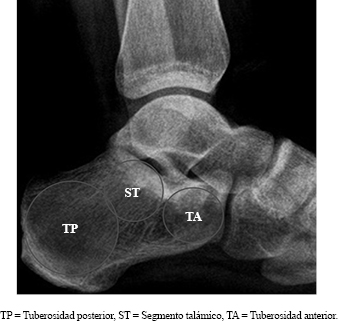

Se planteó un montaje de osteosíntesis basado en los tres fragmentos principales (Figura 1) que se deben fijar en fracturas de calcáneo: (1) la tuberosidad anterior (incluyendo la articulación calcáneo-cuboidea), (2) el segmento talámico (incluyendo la faceta articular subastragalina) y (3) la tuberosidad posterior. Este montaje teórico es el más difundido en el tratamiento de las fracturas mediante el AST.

Figura 1: Rx calcáneo, perfil. Se detallan las tres regiones principales a ser fijadas en el tratamiento de las fracturas.